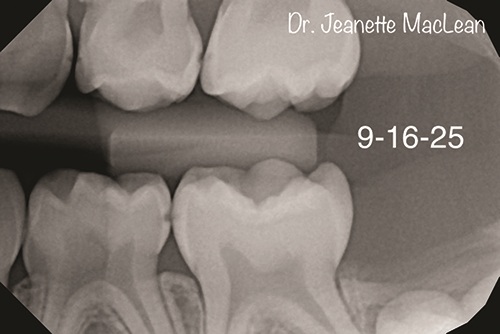

Figs. 1a and 1b: Bitewing radiographs of a second opinion patient (DEXIS Titanium imaging).

Figs. 3a and 3b: Five-month follow-up BWs (DEXIS Titanium imaging).